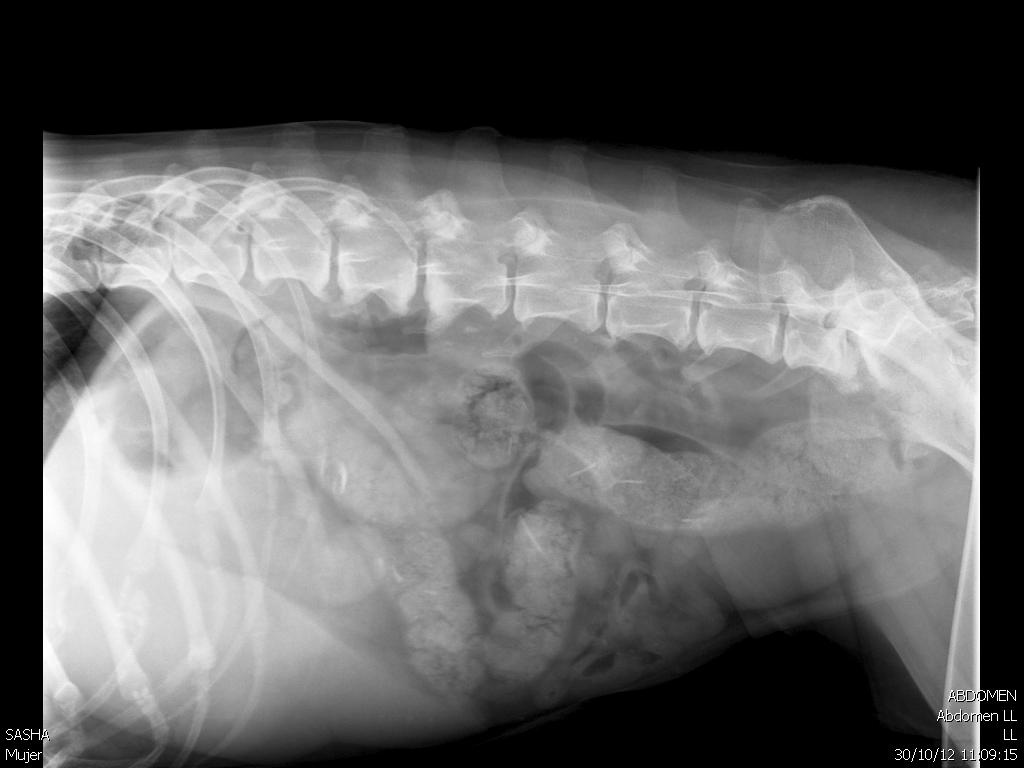

Tumor de bazo en perros

WebEl tumor de bazo es un tipo de cáncer que es común en perros y relativamente raro en los gatos y sus signos a menudo dependen de la localización del tumor, que van desde la. WebEn perros, del 0,3 al 2 por ciento de los tumores registrados se encuentran en las necropsias; el siete por ciento de todos los tumores son malignos; y alrededor del 50 por. WebCáncer de Bazo en perros. Al igual que los seres humanos, los perros y en general los animales domésticos pueden sufrir un sin número de enfermedades, entre. WebLos quistes sebáceos son un tipo de tumor benigno muy común en los perros. En pocas palabras, se producen por la acumulación de sebo, sustancia lipídica cuya función es. WebLas enfermedades más típicas que sufre el bazo son los tumores linfoma y hemangiosarcoma. El hemangiosarcoma es el tumor más frecuente en perros. Los. WebEl tumor de bazo es un tipo de cáncer que es común en perros y relativamente raro y sus signos a menudo dependen de la localización del tumor, que. WebSi es maligno ni que no reventar a terminará en metástasis y también, adiós perro. Si se opera hay mucho riesgo a que muera por su problema cardíaco, pero si sale bien y el.